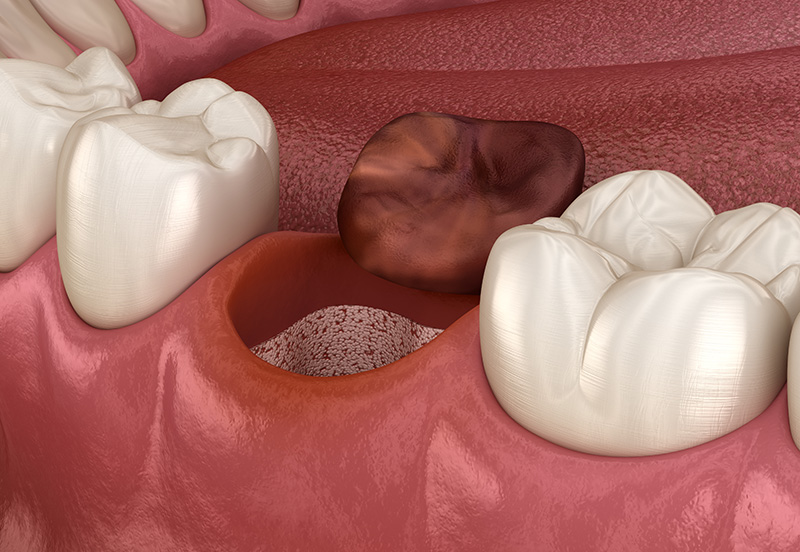

After any tooth extraction, it’s critical that you take special steps to ensure the healing process goes as it should. A blood clot typically forms over an empty tooth socket during healing. If this doesn’t happen or if the blood clot is removed, the bone and nerves below the socket become exposed. This results in a painful complication called dry socket. You can prevent dry socket and ensure a smooth recovery by following the post-extraction guidelines we’ll review in detail with you after your surgery.